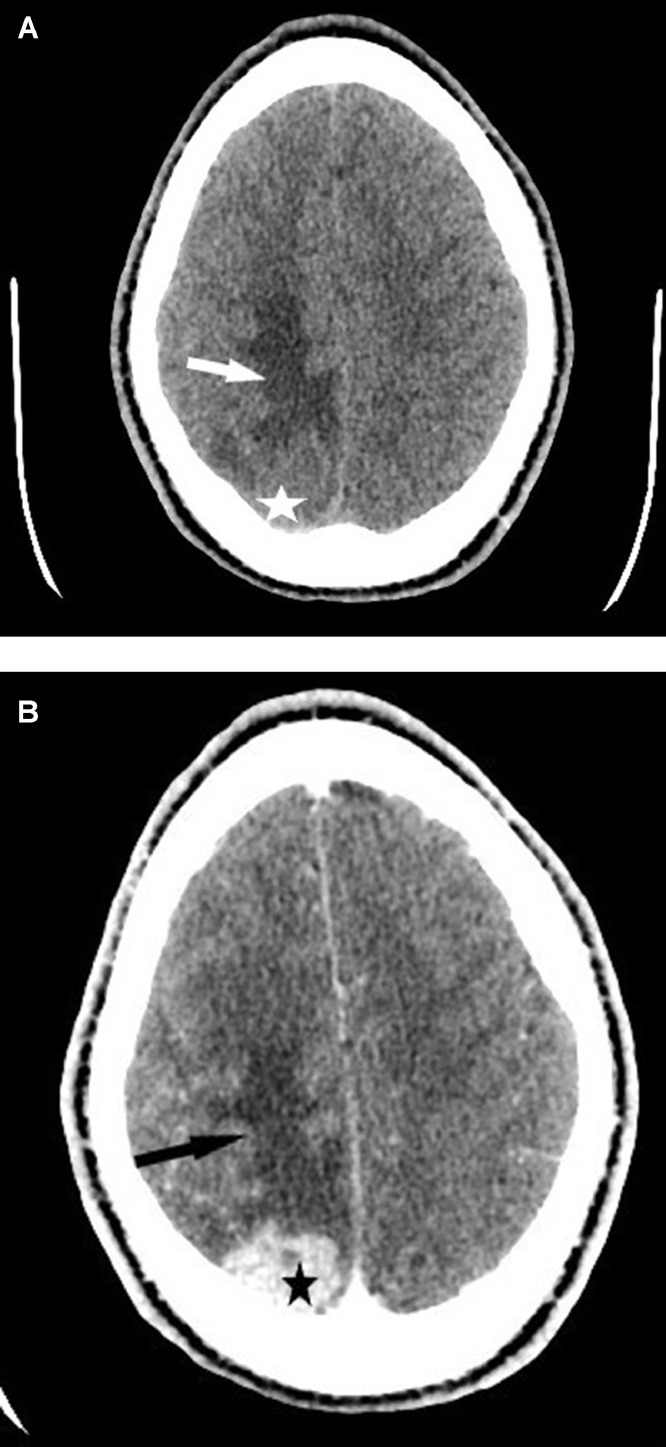

A brain encephalic scan without and with injection revealed an extra-axial right parietal tissue mass taking heterogeneous contrast at the late stage with glove-finger edema without bone reaction to the eye (Fig. 1).

Brain scan in axial section without injection of iodine contrast (A) and with injection (B) revealed an extra-axial right parietal tissue mass (star) taking contrast in a heterogeneous manner at the late stage with glove finger edema (arrow) without bone reaction facing it.